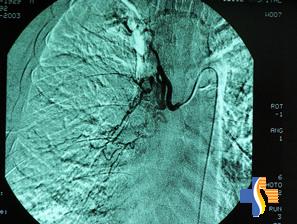

其他輔助檢查:用力肺活量哮喘患者由於患病時間長對症狀出現耐受,呼吸功能的客觀檢查對病情評估尤其重要。分別在臨睡前、夜間覺醒後和清晨時以峰速儀動態測定最大呼氣流量(PEF),同時在午後測定PEF以確定一天中最佳的呼吸功能狀態作為比較基礎值。通過峰速儀的動態觀察,可以了解哮喘狀態,採取正確的處理,可以避免就診時一次測定造成的錯誤判斷,因此應對白天和夜間狀態進行全面評估,同時當患者處於穩定期,動態峰速儀監測常可提示病情變化,應及時提醒病人。通常哮喘患者出現急性發作,可在數天前就有PEF逐漸下降,PEF的變異幅度增大,可及時就診或加以處理。對疑及有睡眠暫停綜合徵者則需進行夜間睡眠監測。